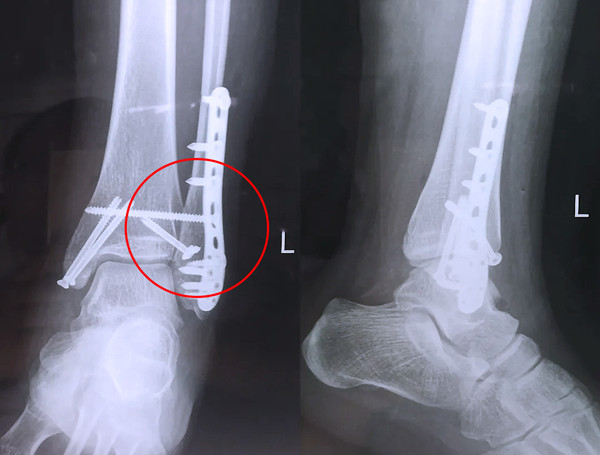

踝關節(jié)骨折在X影像上的表現(xiàn)有很多種。如內踝骨折和外踝骨折,我們可以在影像上看到骨折處的骨折線是不連續(xù)的。還有后踝的骨折,內踝、外踝、后踝聯(lián)合在一起發(fā)生的骨折,我們稱之為“三踝骨折”,這些都是在X影像上能夠顯示出來的。

三踝骨折

有一種特殊類型的踝關節(jié)骨折,可能在X影像平片上就不能顯示出來,它就是脛骨的關節(jié)面往里塌陷,我們又稱之為叫“Pilon骨折”。當它往里塌陷后,我們在X影像平片上可能看不出來它是否塌陷,但是我們在CT上可以360°看到踝關節(jié)的影像,這樣就可以看出患者是否存在踝關節(jié)塌陷的骨折。同樣道理,我們在做Pilon骨折手術的時候,普通二維的X影像并不能判斷我們手術復位情況的好壞,這個時候如果醫(yī)生手上有能夠照三維影像的工具,那么對于醫(yī)生的準確手術是非常有好處的。